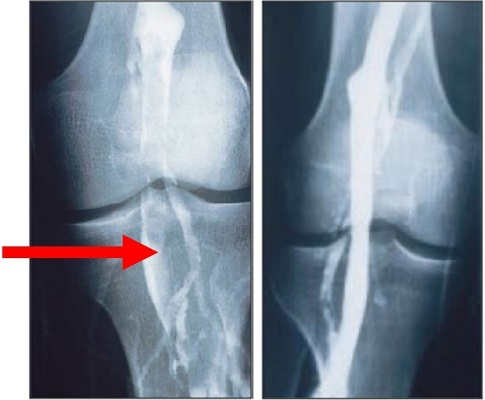

+ Kĩ thuật chuẩn đoán xâm lấn: chụp tĩnh mạch

Chụp tĩnh mạch với chất cản quang rất nhạy cảm nhưng có thể có nhiều biến chứng như thoát ra ngoài mạch chất cản quang, phản ứng dị ứng và huyết khối tĩnh mạch sâu xảy ra sau thủ thuật (ở khoảng 2% bệnh nhân). Đây là phương pháp đáng tin cậy nhất nhưng ngày càng ít được thực hiện.

Hình 4. Huyết khổi tĩnh mạch kheo bên phải (9).